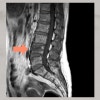

강한 외부 충격으로 인해 허리의 척추뼈에 큰 하중이 가해졌을 때, 허리 뼈가 납작하게 눌려 발생하는 골절입니다.

주로 강한 외상(교통사고, 넘어짐)으로 인해 발생하며, 골밀도가 낮아지는 고령층에서는 골다공증으로 인해 작은 충격으로도 발생하기 쉽다는 특징이 있습니다. 골절 부위는 보통 요추 1번에서부터 4번에서 나타나며, 그중에서 요추 4번 골절은 척추의 하부에 위치해 있어서 특히 보행이나 자세 유지에 영향을 미칩니다.